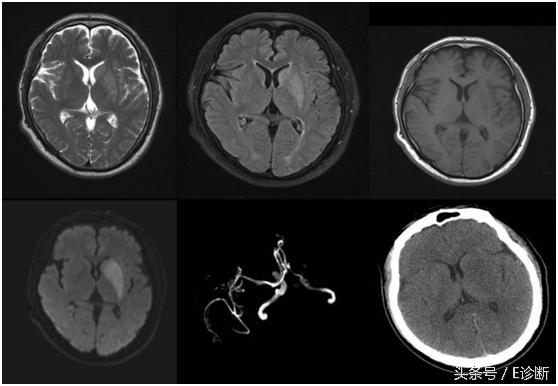

左侧额颞叶、基底节区超急性期脑梗死,发病2小时,T1WI、T2WI及flair像未见异常信号,DWI见高信号,ADC图为低信号,MRA示左侧大脑中动脉闭塞,右侧大脑中动脉狭窄。

左侧基底节区急性期脑梗死,发病24小时,T1WI为稍低信号,T2WI及flair像为稍高信号,DWI为高信号,MRA示左侧大脑中动脉闭塞,此时头CT未见异常改变。

右侧大脑半球多发腔隙性脑梗塞,MRA示右侧大脑中动脉狭窄,PWI示CBF和CBV正常,MTT及TTP延长